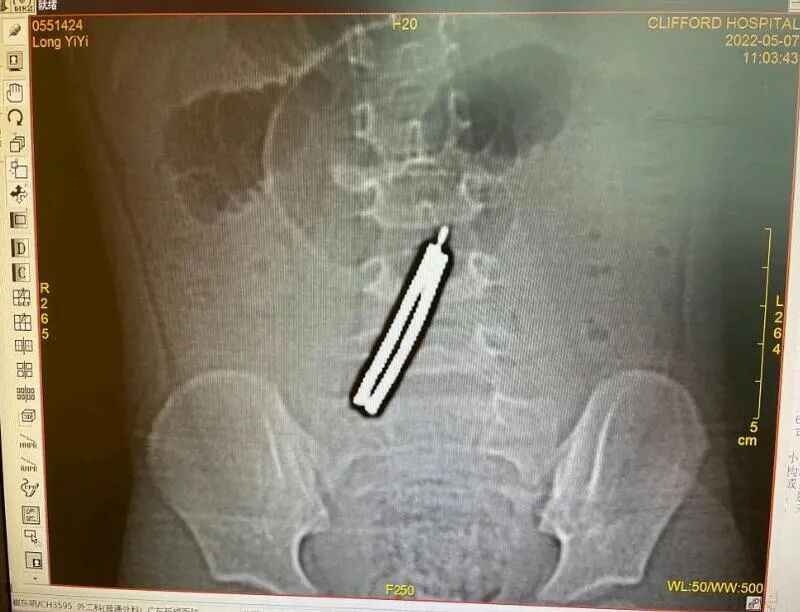

近日,3岁半的娜娜(化名)腹痛呕吐,还发高烧,经CT检查发现,她腹中竟藏着10块磁力棒,1颗螺丝钉!异物在消化道“你追我赶”“相互吸引”,串成一个约7厘米的“发夹”,磨穿了5个洞,非常危险。为防止病情恶化,普通外科医生迅速为女童开展手术,将异物顺利取出,终于成功脱险。

不久前,家住广州番禺区的女童娜娜接连几天都喊肚子疼,还反复呕吐和发高烧,这可把家长急坏了,该不会是吃错了什么东西吧?家长连忙带着孩子来到广东祈福医院儿科就诊。万万没想到,做了CT检查让医生和家长大吃一惊:娜娜的肠子里竟然“躺”着一个“不明物体”!

CT发现娜娜肚子里有异物

是什么时候吃下去的?吃下了什么东西?家长也搞不清楚,通过CT图的形状判断,家长怀疑可能误吞了发夹。医生在询问孩子经常玩什么玩具后,高度怀疑是娜娜最近的新宠“磁力棒”在捣鬼!吞下的磁力棒相吸,可导致肠穿孔,不及时处理将出现感染性休克,情况十分危急。

术前准备就绪后,在麻醉师的协助下,医生通过小肠异物取出术,取腹部小切口进入腹腔,发现娜娜肚子共有10块磁力棒和1颗螺丝钉,由于磁性的作用,它们在消化道中“相互吸引”,进而将小肠磨穿了5个洞!